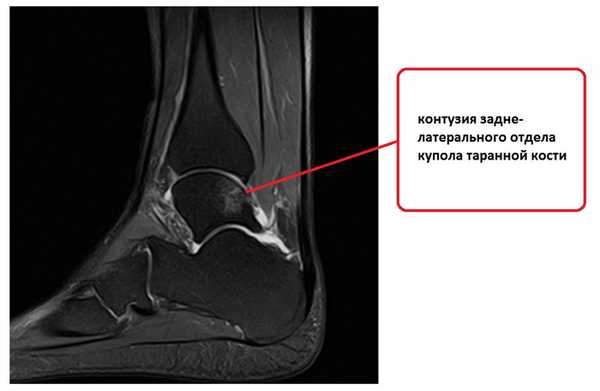

На этом этапе пациентка лечилась по стандартному сценарию «растяжение голеностопа». Носила ортез, мазала голеностоп вольтареном и лиотоном, разгружала его при помощи трости. Но в связи с длительно сохраняющимся болевым синдромом было выполнено МРТ, при котором диагностирован застарелый разрыв передней таранно-малоберцовой связки, пяточно-малоберцовой связки правого голеностопного сустава, контузионное повреждение латеральных отделов таранной кости.